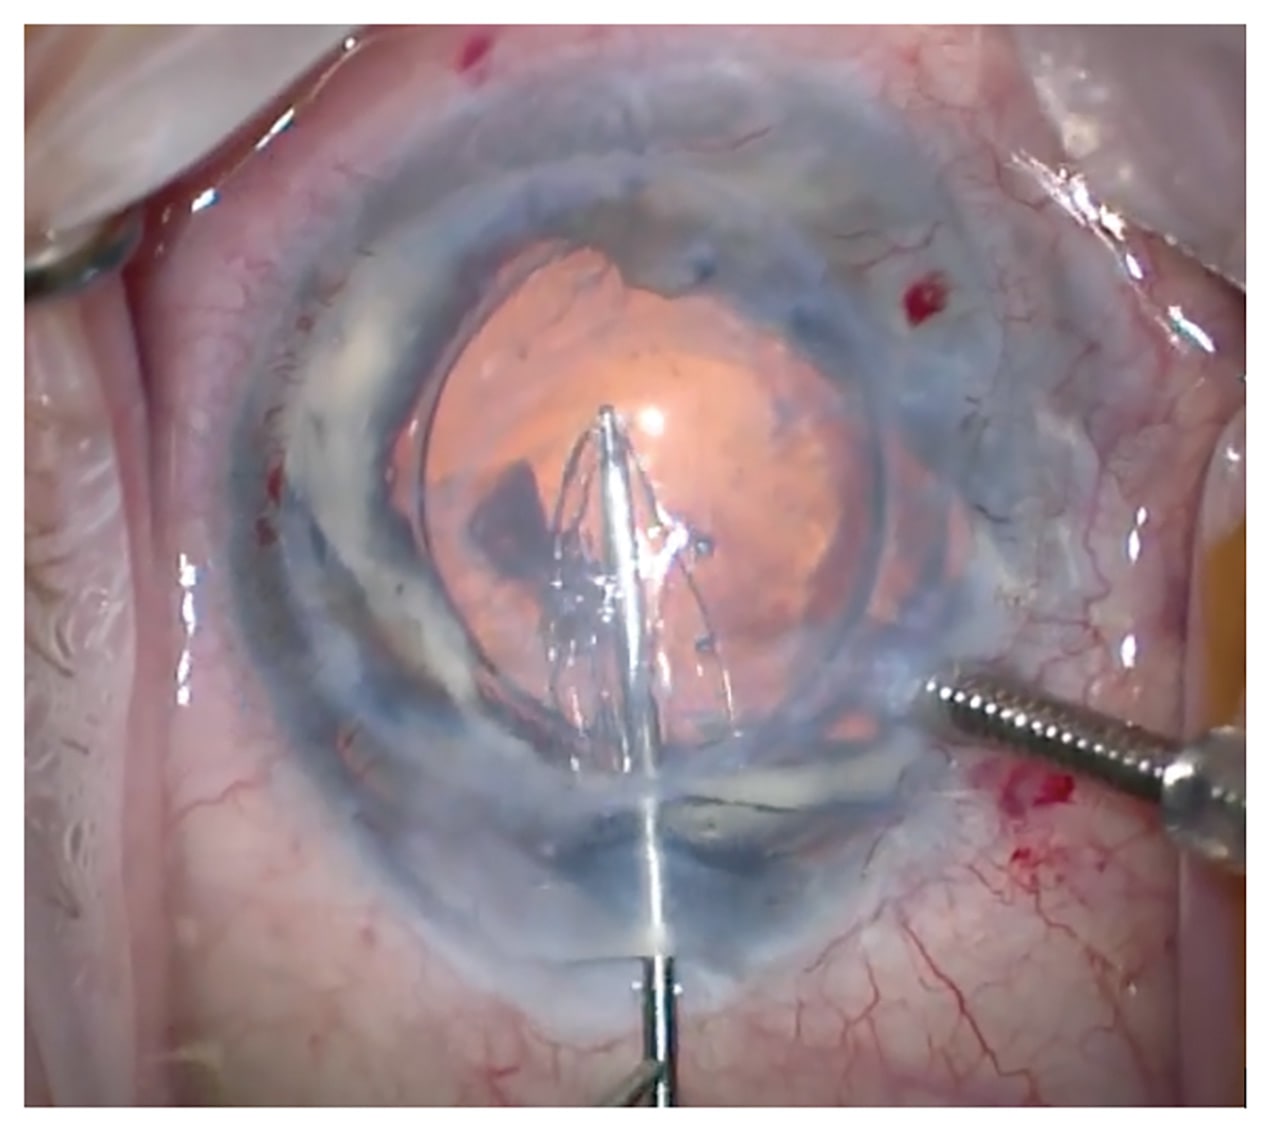

In comparison to using donor tissue, the manipulation of the implant is very simple. The graft can be handled directly with no fear of losing cells (Figure 1). Initially, the grafts had a tendency to detach requiring multiple rebubbles so the surgical technique was adapted to include a longer acting gas tamponade (C3F8) and a fixation suture (Figure 2). I strongly remind the patients not to rub their eyes. The suture can be removed a few weeks later at the slit lamp and this has significantly reduced the detachment rate. Postoperative steroids can also be reduced and stopped, unlike in endothelial keratoplasty.